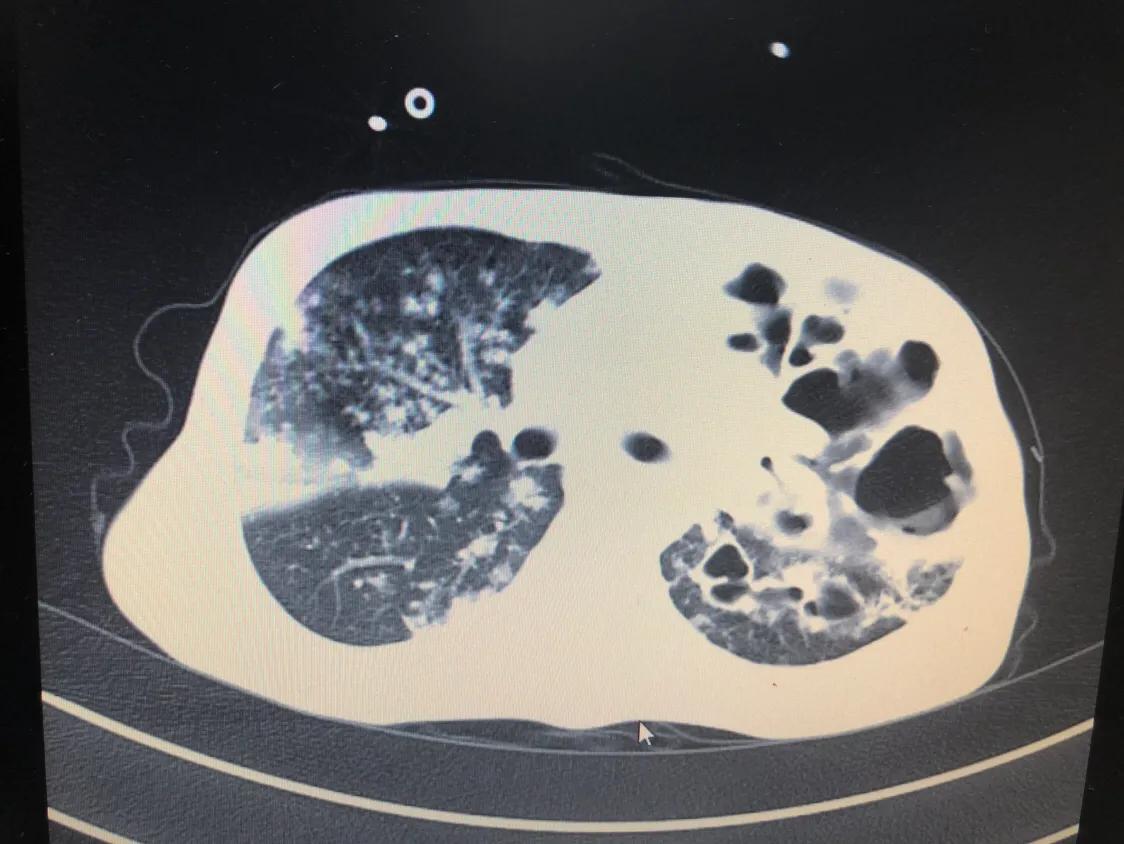

影像学检查包括X线胸片和胸部CT。前面讲的几种主要类型的肺结核,各自有不同的表现:

- 急性血行播散型肺结核在X线胸片上表现为散布于两肺野的,分布、密度、大小“三均匀”的粟粒状阴影,故又叫粟粒型肺结核。

- 继发性肺结核是最常见的,其X线表现也是最复杂、多变的,有时很难跟普通的肺炎相鉴别。

CT相对于胸部X线片来说,会更清楚,分辨率更高,能看到更小的病灶,但存在着辐射比胸片更大的缺点。

肺部影像学检查,大多数情况下能提供基本准确的肺结核的诊断,但是仍然有少部分人需要完善进一步的检查,才能使结论更可靠。

诊断性抗结核治疗后,最好每个月检测一次肺部的X线片或者CT,如果病灶有吸收,说明结核的倾向更大;如果两个月没有任何吸收,则要重新考虑诊断。

- 胸片或CT显示与活动性肺结核相符的病变 ;